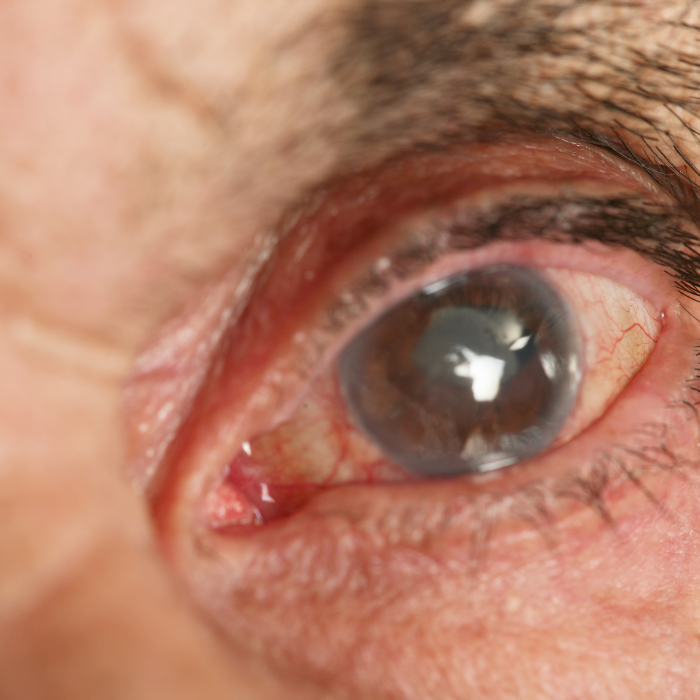

La chirurgia del glaucoma rappresenta una soluzione efficace nei casi in cui la terapia farmacologica o la laser terapia selettiva (SLT) non riescono più a mantenere la pressione intraoculare (PIO) entro valori sicuri.

la pressione oculare rimane troppo elevata nonostante l’uso corretto dei colliri o della laser terapia;

il campo visivo continua a peggiorare;

il glaucoma si presenta in forma avanzata o a progressione rapida.

Il Dr. Lo Schiavo Elia valuta con attenzione ogni caso attraverso esami diagnostici approfonditi — tonometria, OCT, campo visivo, gonioscopia — per individuare la tecnica più adatta al tipo di glaucoma e alle caratteristiche anatomiche dell’occhio.